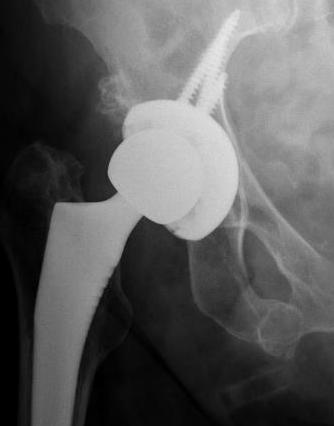

Screw fixation

Goal

Transacetabular screw fixation to augment initial cup stability

Safe zones

- anatomical cadaveric study

- line ASIS to to ischial tuberosity through center of acetabulum

- line perpendicular to this creates four quadrants

- safe quadrants are the posterior quadrants

PS quadrant

- sciatic nerve / superior gluteal nerve and vessels in danger at greater sciatic notch

- aim screw between 2 cortices of ilium

- direct towards sacro-iliac joint

- can tolerate 85 mm screws